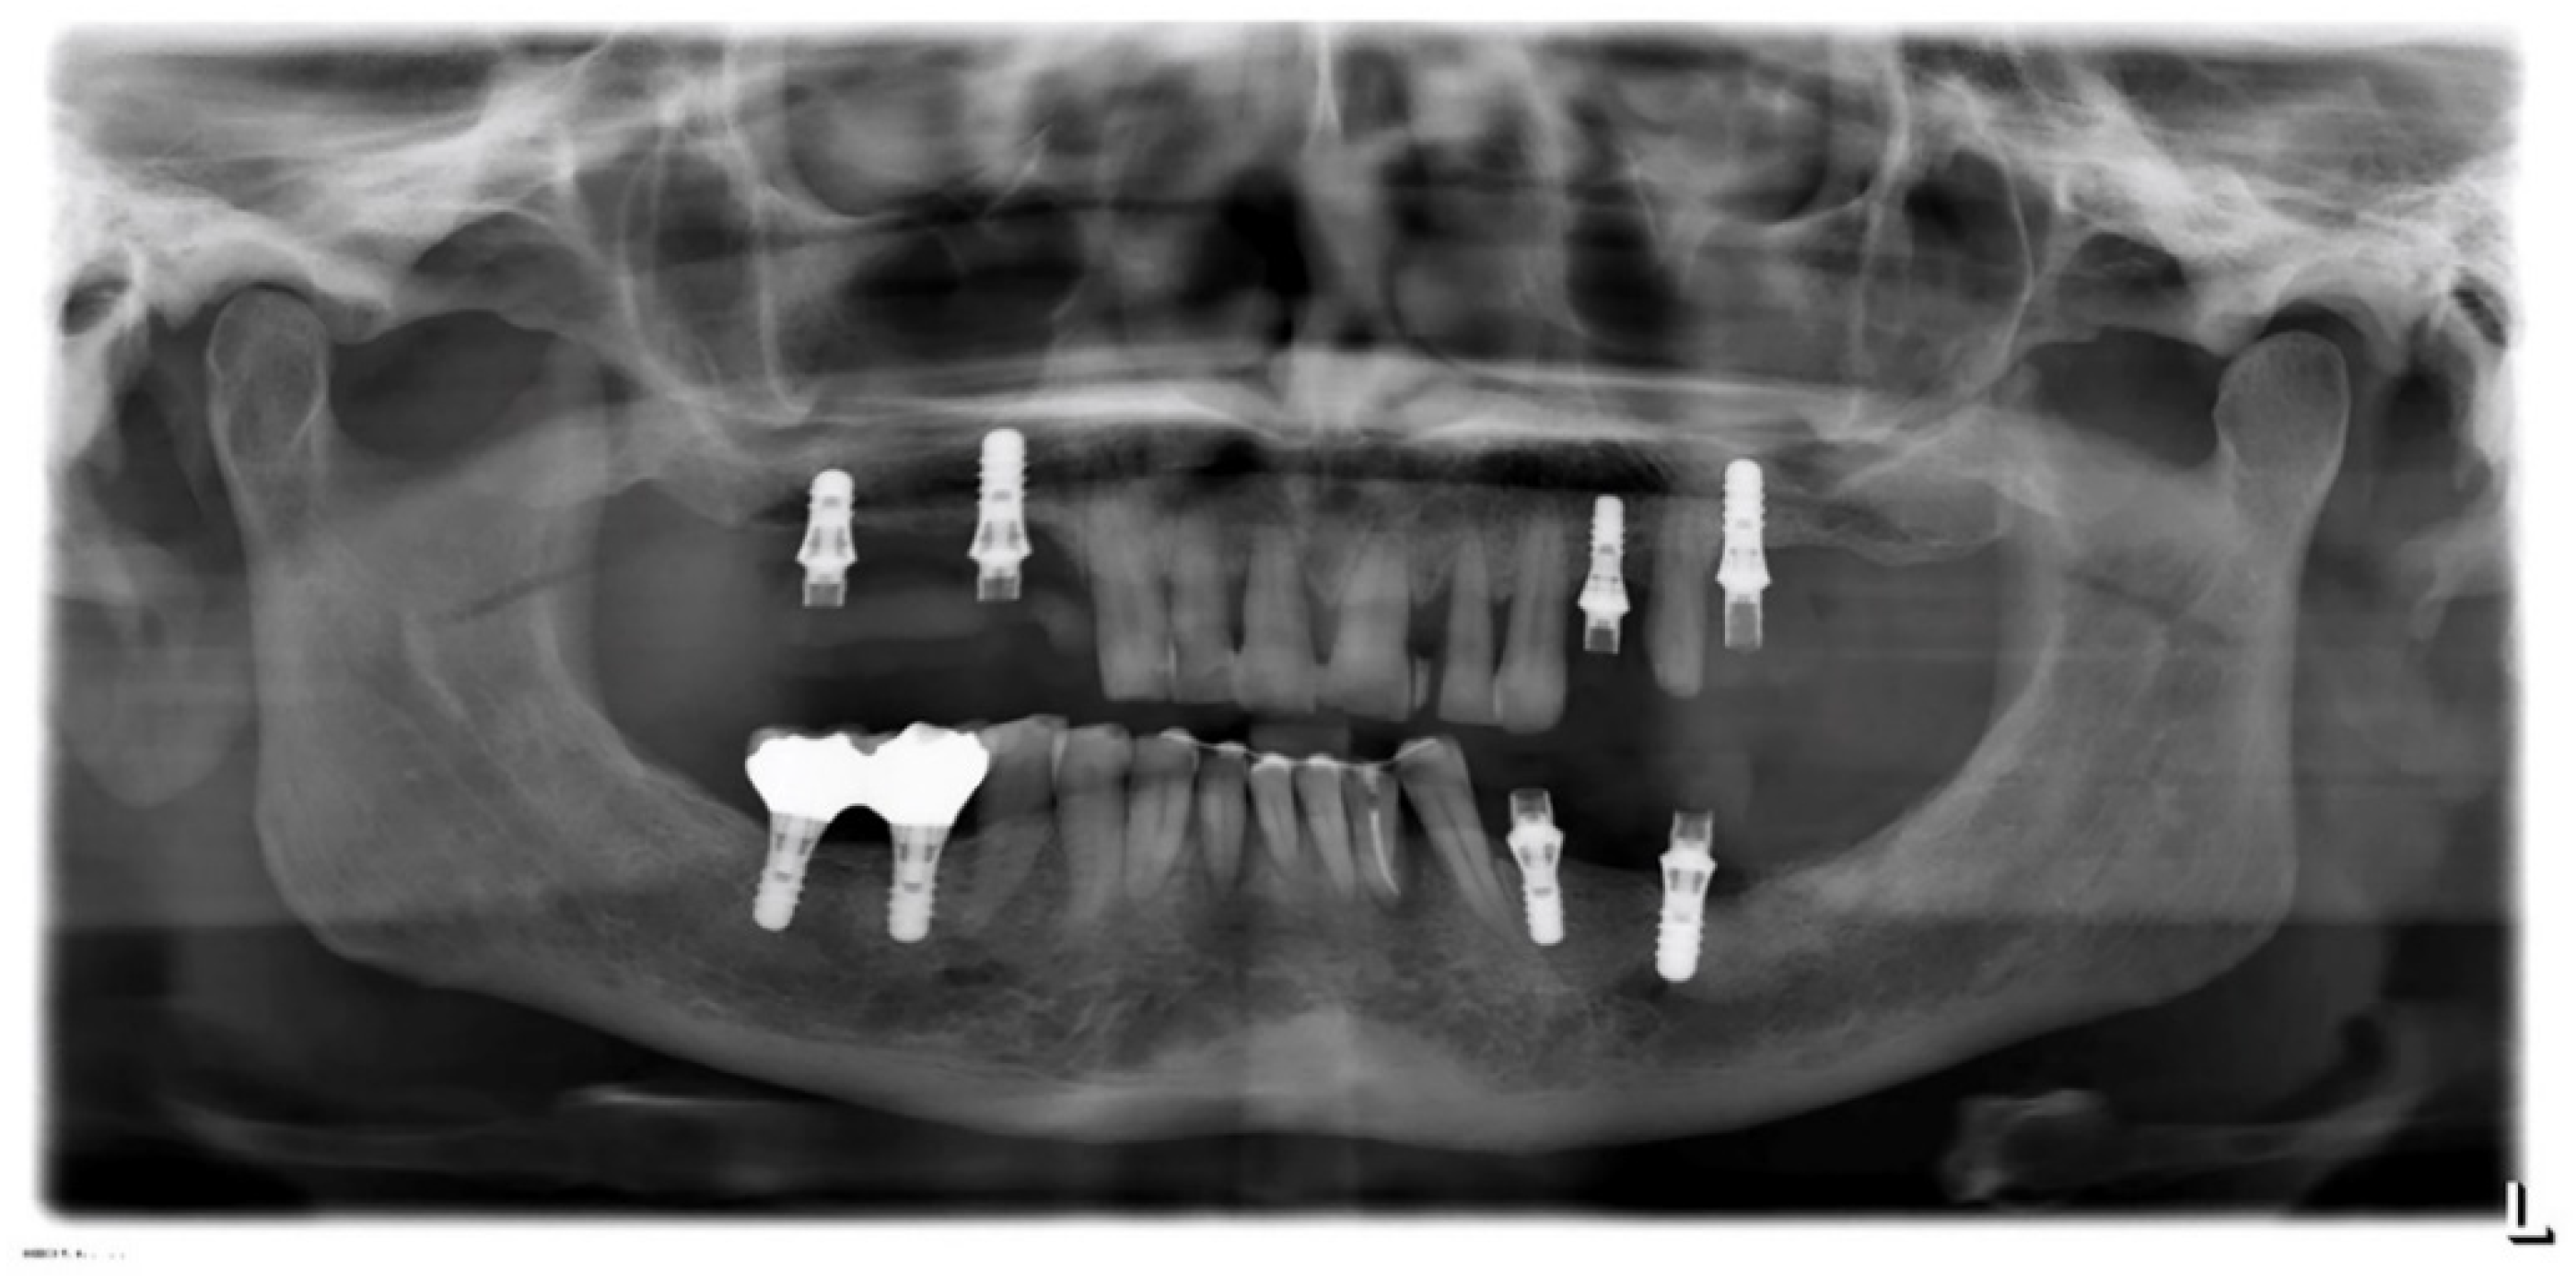

1.3. Case 3

A 59-year-old female attended a consultation complaining of aesthetic dissatisfaction with the diastemas between her upper frontal teeth and difficulty speaking and chewing. The patient wore provisional crowns supported by implants in the posterior regions (Figure 15). After an accurate diagnostic phase, which involved (1) intra-oral radiographic status, (2) probing of natural elements and implants, and (3) mobility and occlusal evaluation, the patient was classified as affected by periodontitis of stage 4 (Figure 16). Strong occlusal contacts were detected between upper and lower incisors, suggesting that occlusal trauma could contribute to the severity of the incisors’ mobility. In this regard, the provisional posterior crowns were maintaining the previous (reduced) vertical dimension without mitigating anterior contacts.

Figure 16. Case 3. Panorex.